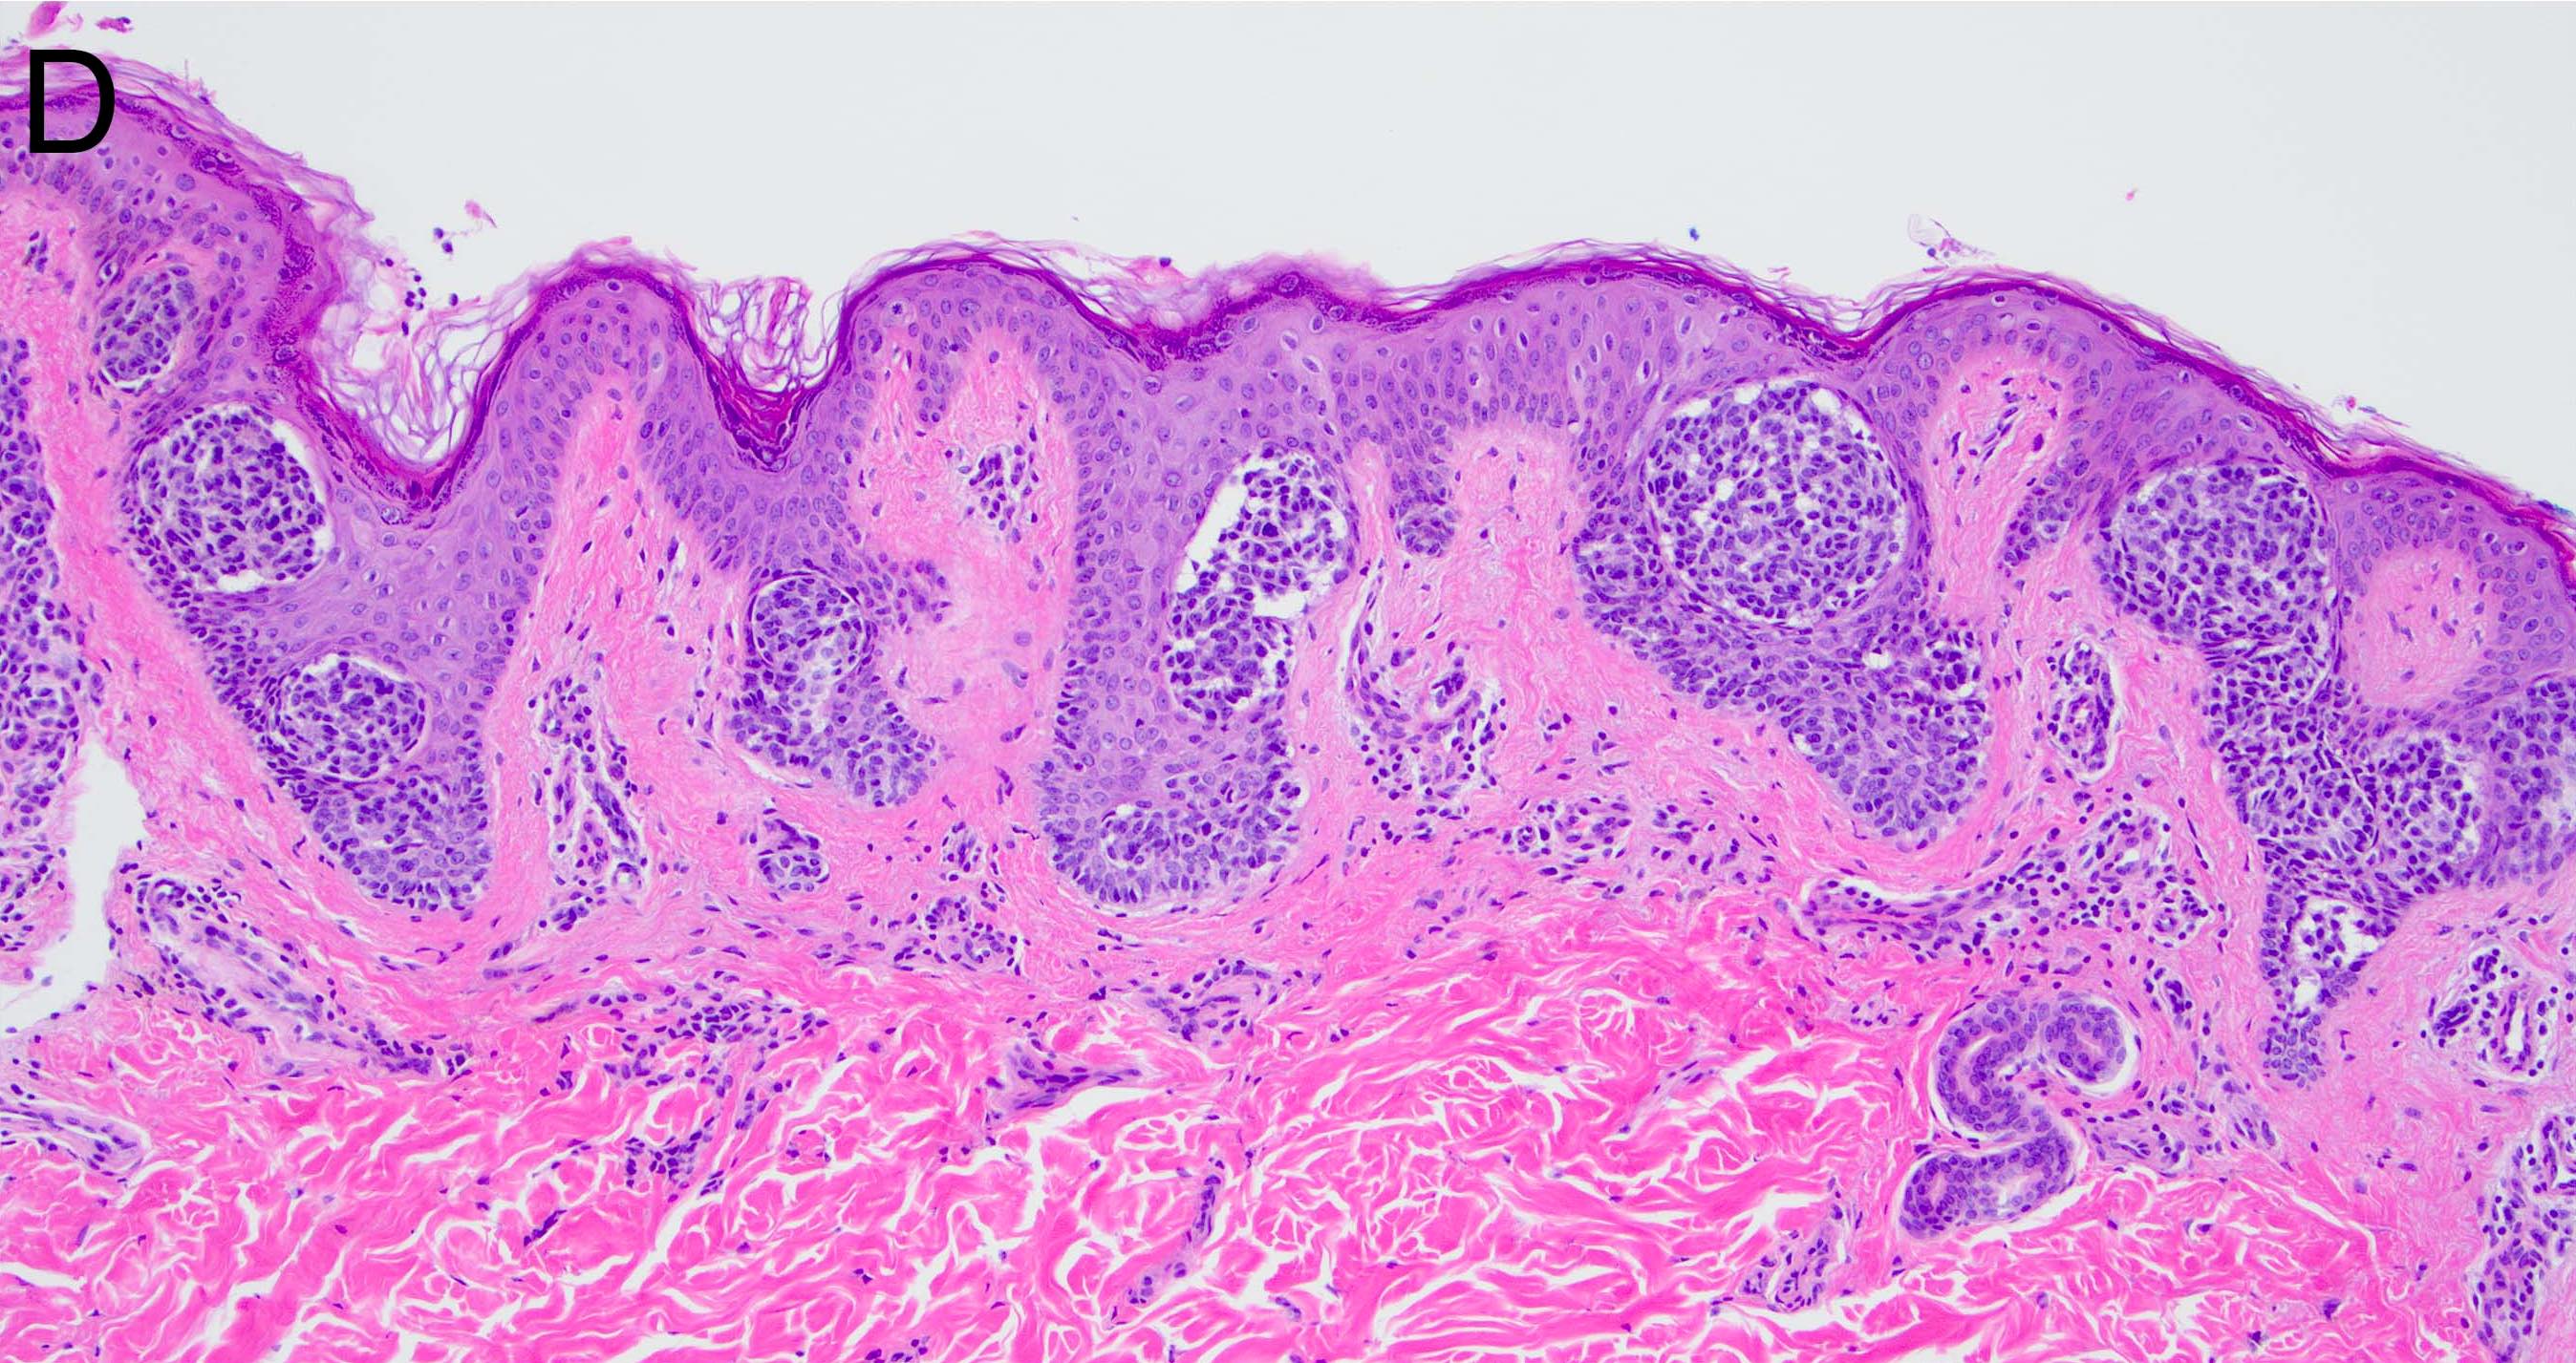

- Melanocytic nevi of the ear (Am J Dermatopathol 2005;27:111):

- Frequently display poor lateral circumscription

- Junctional nests may not be centered and can be placed within inter-rete spaces and along sides of rete

- May display pagetoid spread

- Irregular nesting pattern

- Cytologic atypia that is uniformly present may be seen

- May induce a host inflammatory response

- Melanocytic nevi of the breast (Am J Dermatopathol 2016;38:867):

- May contain large irregular dyshesive nests in close proximity to one another

- Junctional nests may not be centered and can be placed within inter-rete spaces and along sides of rete

- Nests may have variable pigmentation (results in globules seen on dermoscopic exam)

- Nests may have prominent horizontal streaming resulting in rete blunting or epidermal effacement

- Cytologic atypia is common

- Maturation with melanocyte descent should be retained

Microscopic (histologic) images